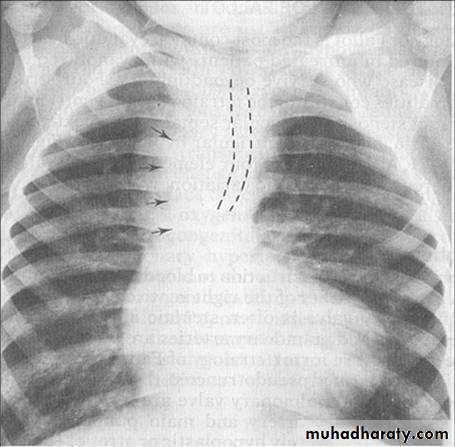

CXR

Infants with severe disease: cardiomegaly, heart failure

Notching posterior ribs: erosion by collaterals

“3” Sign: Indentation of aortic wall with pre and poststenotic dilatation